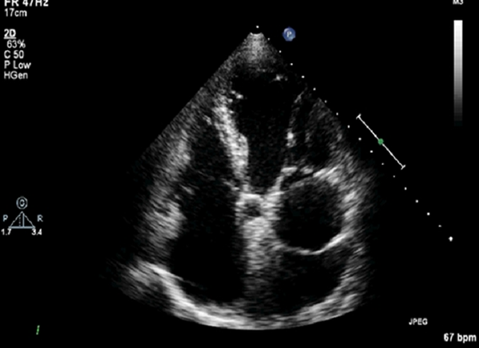

what is this?

cor triatriatum